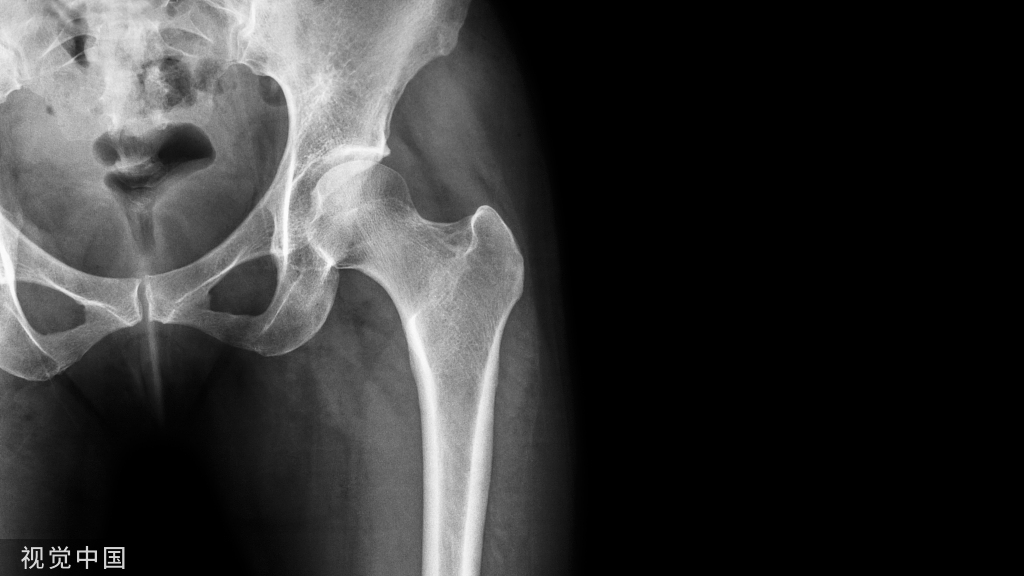

腰臀部的疼痛、压痛以及明显的下肢放射痛,无论是医生或者患者很多时候都会考虑腰椎间盘突出症,此时CT或者MR可提示椎间盘的情况,此外另有两类疾病可以考虑,那就是梨状肌综合征以及臀中肌损伤

梨状肌大部起于第2~4骶前孔外侧,出骨盆后,有周围肌纤维加入,几乎充满坐骨大孔,由此出盆移行为肌腱,紧贴髋关节囊的后上部,向外止于大转子上缘的后部。

臀中肌起于髂骨翼外面,止点于股骨大转子,臀中肌后部位于臀大肌深层,为羽状肌。

梨状肌穿出坐骨大孔,与坐骨神经的解剖关系非常密切,梨状肌若受损伤或梨状肌与坐骨神经解剖结构发生变异就可能使坐骨神经受到挤压而发生各种症状。